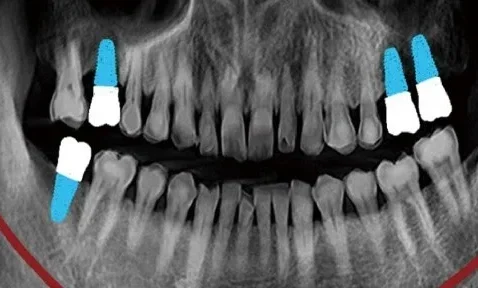

Modul panoramic digital oferă imagini clare și uniforme, realizate cu detector CMOS de înaltă sensibilitate, având o rezoluție de 120 µm/pixel.

Precizie în diagnostic: voxel de 200 µm pentru CBCT și rezoluție panoramică de 120 µm/pixel.

Versatilitate clinică: potrivit pentru implantologie, chirurgie orală, sinus lift, planificare pre-protetică.